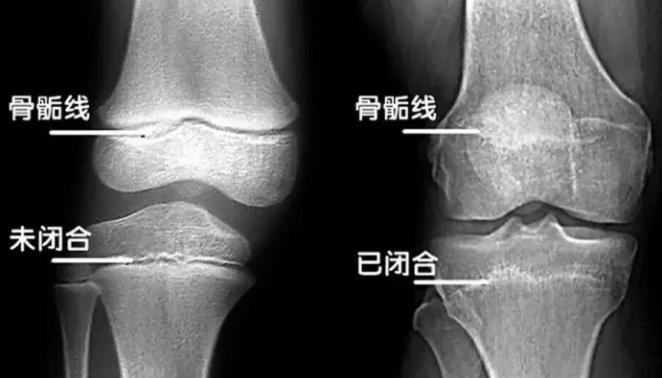

测骨龄,需要借助于骨骼在X光摄像中的特定图像来确定。X光片中,可以看到骨骺[hóu]线的状态, 当骨骺线完全闭合后,骨骼就停止生长了,身高就固定了。

骨龄是有生长时间的,一旦骨骺线完全闭合,骨骼就停止生长了。如果寄希望于以后长高,忽略眼前的矮小,万一没有长高,想再去人工干预也无济于事了。 骨骺线闭合时间:通常女孩17岁,男孩18岁。